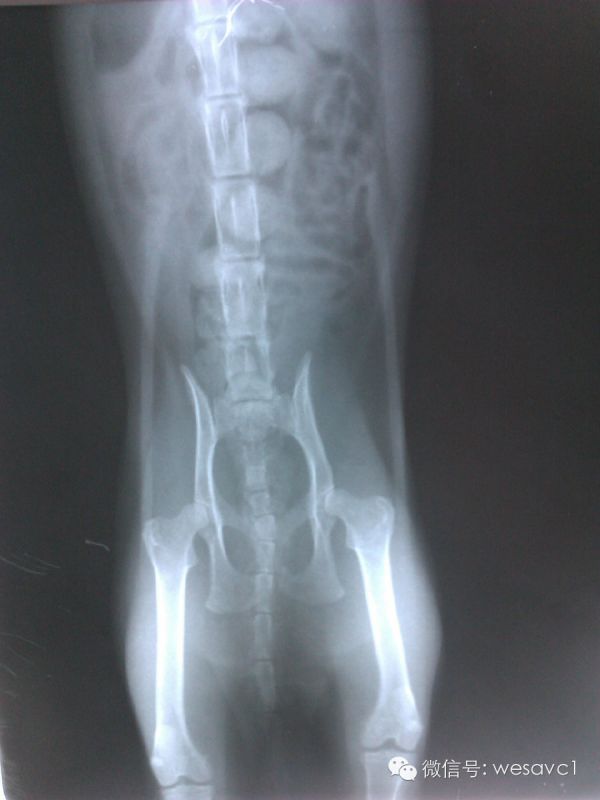

3.3.4 X光检查:

图

根据其病史、临床基本检查以及血常规、生化、血气分析、影像学检查结果判断,该猫除了存在营养状况较差、轻度的脱水以及有代谢性碱中毒外,未见其他明显的异常。排除掉能导致的猫食欲不好的一些疾病因素,同时考虑到猫独立性、领域性以及应激性强的特点,因此诊断为从一个熟悉的环境到一个陌生的环境的应激因素引起的食欲下降进而发展成的厌食症。